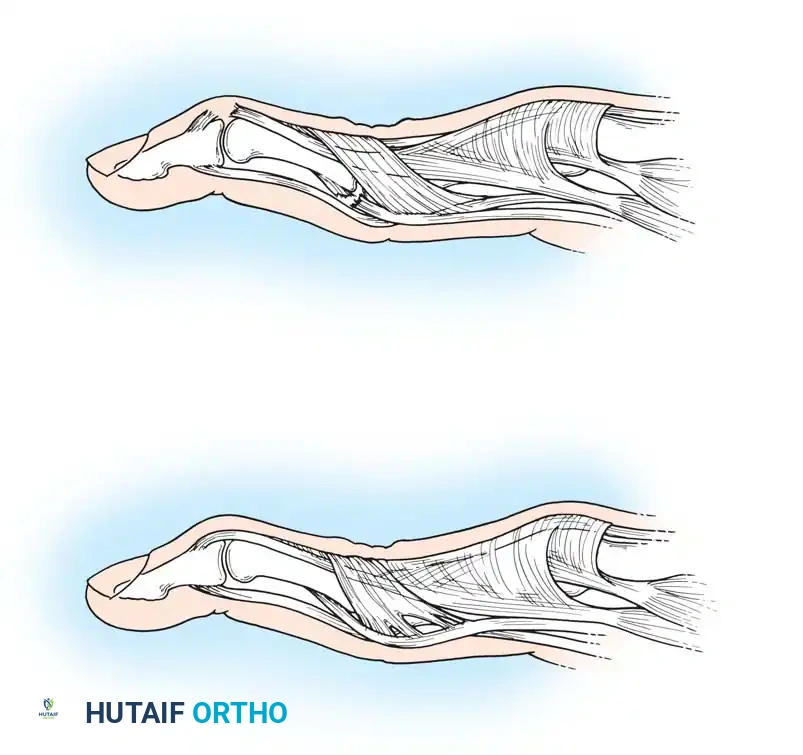

The intrinsic plus deformity is characterized by flexion of the metacarpophalangeal (MCP) joints and extension of the proximal interphalangeal (PIP) joints. It is caused by the tightness, spasm, and eventual ischemic contracture of the intrinsic muscles (lumbricals and interossei) secondary to rheumatoid inflammation.

In hands with a fixed intrinsic plus deformity, the PIP joint cannot be flexed while the MCP joint is fully extended. This deformity frequently develops in combination with volar subluxation of the MCP joints and ulnar deviation of the fingers.

When indicated, intrinsic tightness may be released in conjunction with MCP synovectomy by mobilization of the lateral bands. If severe degeneration of the MCP joints requires arthroplasty, the resection of the metacarpal head often shortens the skeletal framework sufficiently to relax the intrinsic mechanism without requiring a formal release.

Anatomical illustration of the intrinsic musculature and its relationship to the extensor hood mechanism.